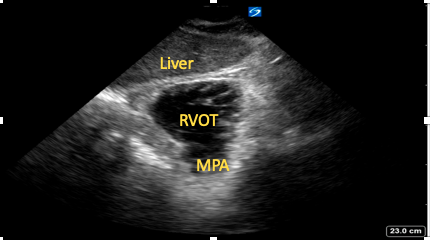

Subcostal Right Ventrical Outflow Tract View

Starting from the SC four-chamber view, cephalad tilting of the transducer is performed until the right ventricular outflow tract (RVOT) and pulmonary artery are visualized (Figure 11). Good cursor alignment means Doppler analysis of both the RVOT and pulmonary valve is often possible from this view.15

Figure 11. Subcostal

right ventricular outflow tract view.

RVOT=right ventricular outflow tract,

MPA=main pulmonary artery